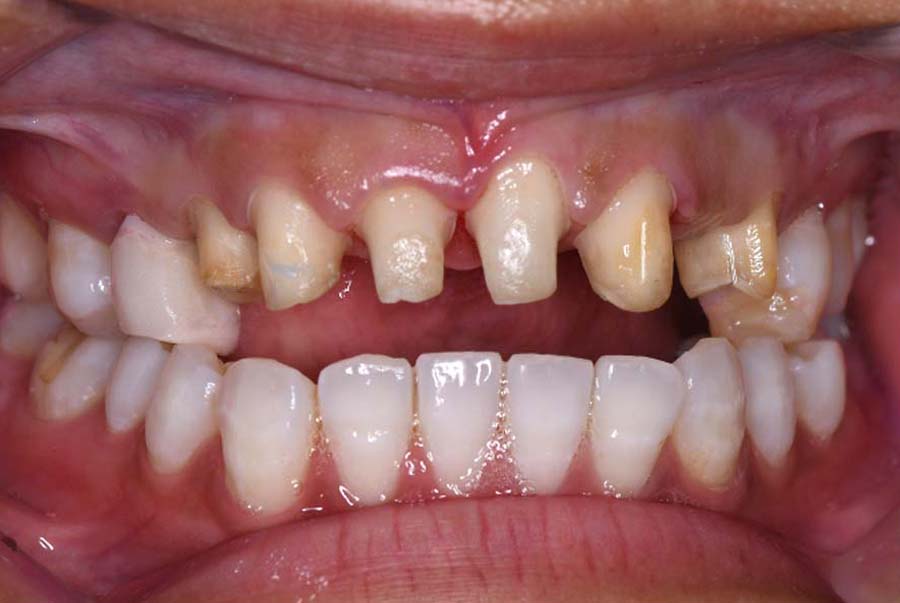

主訴 噛み合わせが悪い

治療内容 ①スプリントを装着

②副子を装着

③2024年4月 口腔内反映開始

④副子を入れた状態の所まで咬合を挙上

(バイトアップ)

⑤2024年5月 上顎前歯部8本へ仮歯(TEK)

を装着

初診日 2023年10月12日